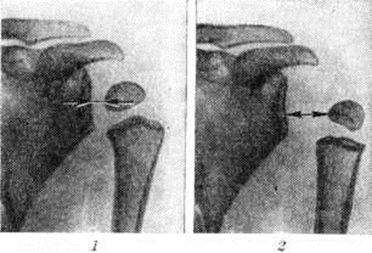

Дюшенна – Эрба параличДюшенна – Эрба паралич (G. В. A. Duchenne, французский невропатолог, 1806—1875; W. Н. Erb, немецкий врач, 1840—1921) — паралич верхнего ствола (от IV, V и VI спинномозговых нервов) плечевого сплетения. В 1872 год. Г. Дюшенн описал верхний тип паралича плечевого сплетения, который он наблюдал у новорожденных детей после некоторых акушерских манипуляций. Через 4 года В. Эрб дал клинической, и анатомическую картину поражения верхнего ствола плечевого сплетения у взрослых и объяснил патогенез заболевания. Этиология и патогенезПричиной Дюшенна – Эрба паралич у грудных детей обычно является родовая травма (смотри полный свод знаний). Плечевое сплетение может повреждаться, когда акушер вводит палец под мышку, чтобы освободить плечико, или при манипуляциях щипцами — резком повороте и натяжении головки плода. При этом сплетение чрезмерно растягивается и разрывается. Дюшенна – Эрба паралич у новорожденных иногда может быть обусловлен родовой травмой шейного отдела позвоночника и спинного мозга. У детей более старшего возраста и у взрослых Дюшенна – Эрба паралич возникает вследствие резкой тракции за руку, при ушибе шеи или области плечевого сустава, а также при резком запрокидывании руки за голову во время сна. Верхний ствол плечевого сплетения часто повреждается при огнестрельных ранениях шеи: корешки CV - VI идут круто вниз, они длиннее остальных корешков и связаны вместе на первом участке сплетения, где и повреждаются. Кроме того, Дюшенна – Эрба паралич могут вызвать различные инфекции, чаще всего грипп. Патологическая анатомияПри морфологически исследовании находят типичную картину травматического или инфекционного неврита (смотри полный свод знаний) — разволокнение и дистрофические изменения нервных волокон, признаки демиелинизации. При травме шейного отдела позвоночника и спинного мозга в отдельных случаях обнаруживают на уровне V—VI шейных сегментов гематомиелические очаги (смотри полный свод знаний: Гематомиелия). Клиническая картина заболевания весьма характерна. Она проявляется экстензией руки и поворотом её внутрь. При этом параличе поражены подмышечный (n. axillaris), мышечно-кожный (п. musculocutaneus) и частично лучевой (п. radialis) нервы, вследствие чего выпадает иннервация в основном следующих мышц: дельтовидной (m. deltoideus), двуглавой мышцы плеча (m. biceps), плечевой (m. brachialis), плечелучевой (m. brachioradialis). Больной не может поднять и отвести плечо, согнуть руку в локтевом суставе, супинация затруднена. Указанные мышцы атрофируются, рука кажется длиннее здоровой вследствие подвывиха плеча. Чувствительность снижена вдоль всей латеральной поверхности верхней конечности в форме узкой ленты, зона чувствительности соседних корешков частично перекрывает поражённые области корешков CV - VI. Характерна болезненность, особенно в остром периоде, при надавливании в точке Эрба (над ключицей кнаружи от места прикрепления грудиноключично-сосцевидной мышцы). Имеются изменения и со стороны сухожильных рефлексов; обычно исчезает рефлекс с двуглавой мышцы. Рентгенологическая картинаРентгенологическое исследование позволяет установить отклонения в состоянии костей плечевого сустава в начальных фазах заболевания и проследить за дальнейшими их изменениями. Уже в первые месяцы жизни до появления ядер окостенения головки плечевой кости рентгенологически у ребёнка можно обнаружить симптом разболтанности плечевого сустава, основным признаком которого является увеличение расстояния между краем проксимального метафиза плечевой кости и суставной впадиной лопатки, что сравнительно легко устанавливается при сопоставлении рентгенограмм (или электрорентгенограмм) больного сустава с симметричным здоровым (рисунок 1). После появления ядра окостенения головки плеча изучению и сравнению подлежит расстояние от ядра окостенения до суставной впадины. |

В связи с разболтанностью сустава и поворотом руки внутрь происходит проекционное смещение ядра окостенения головки плеча (рисунок 2), которое иногда приводит к ошибочному заключению о развитии при Дюшенна – Эрба паралич эпифизеолиза. В дальнейшем отчётливо выявляется остеопороз (смотри полный свод знаний) и атрофия костей плечевого пояса, особенно головки плеча и суставного отростка лопатки. Сравнительное изучение рентгенограмм плечевых суставов ребёнка показывает, что кости больной конечности уменьшены в размерах, порозны и атрофичны.